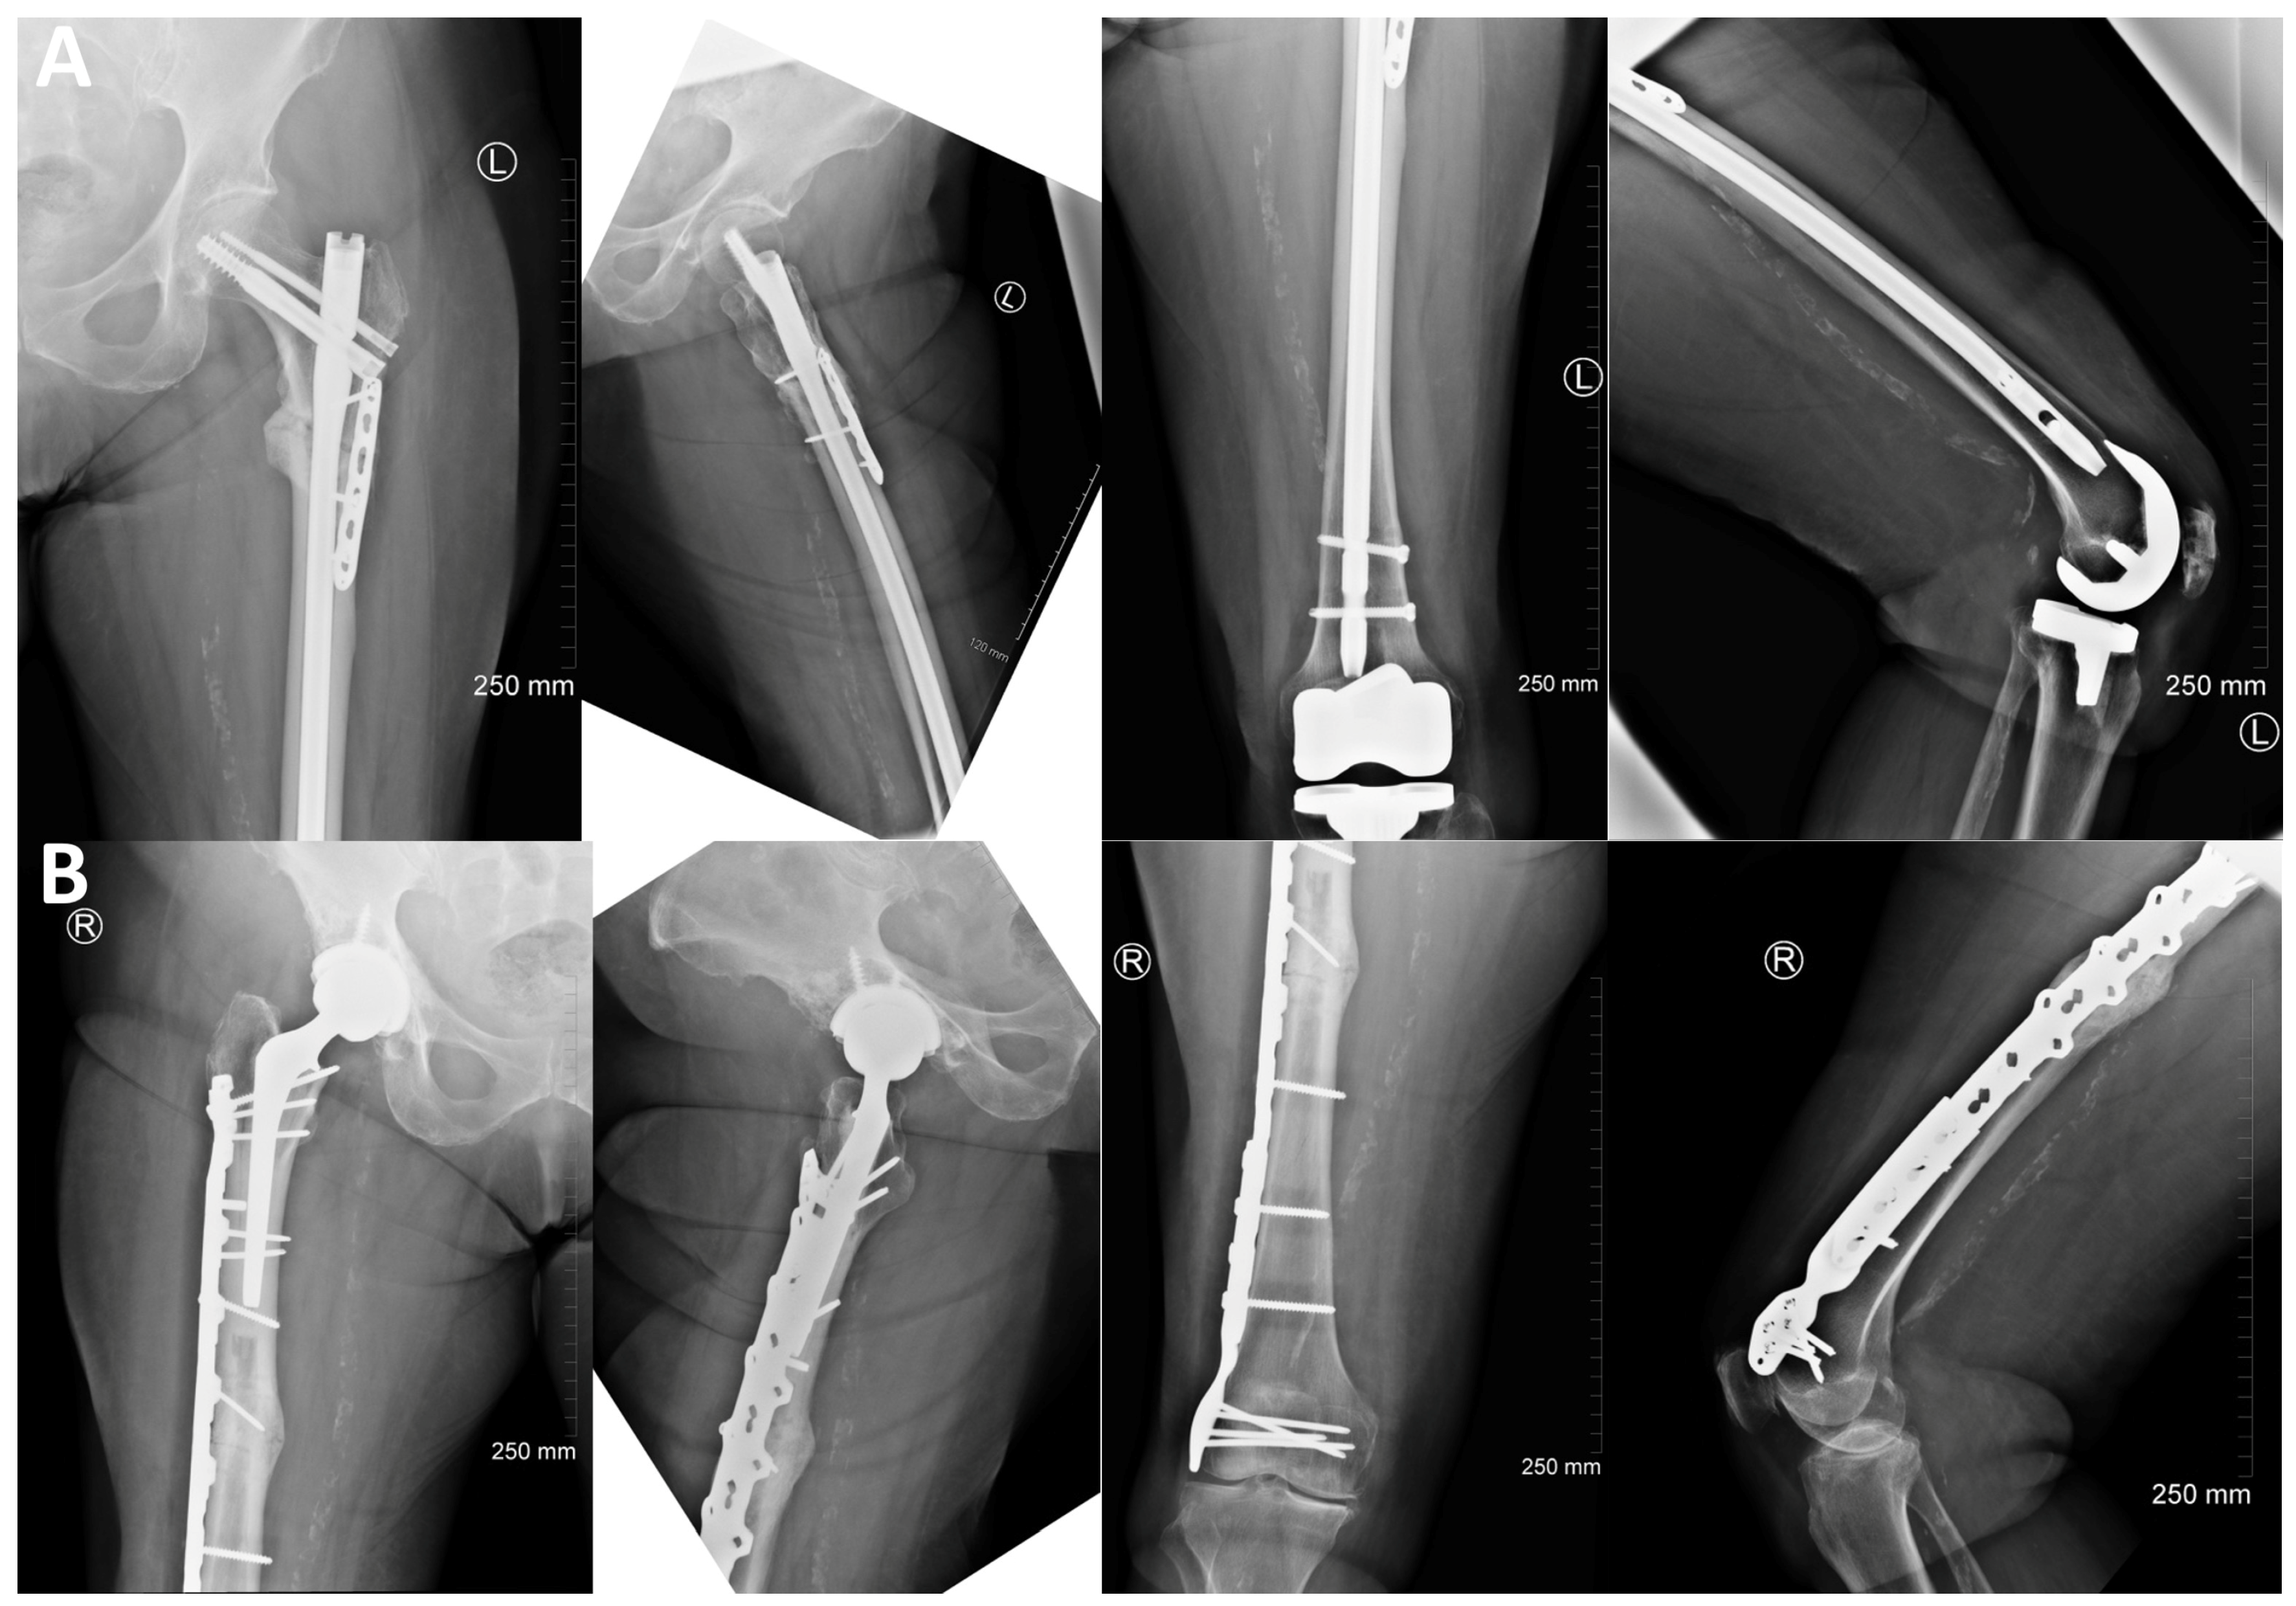

2. Case Description